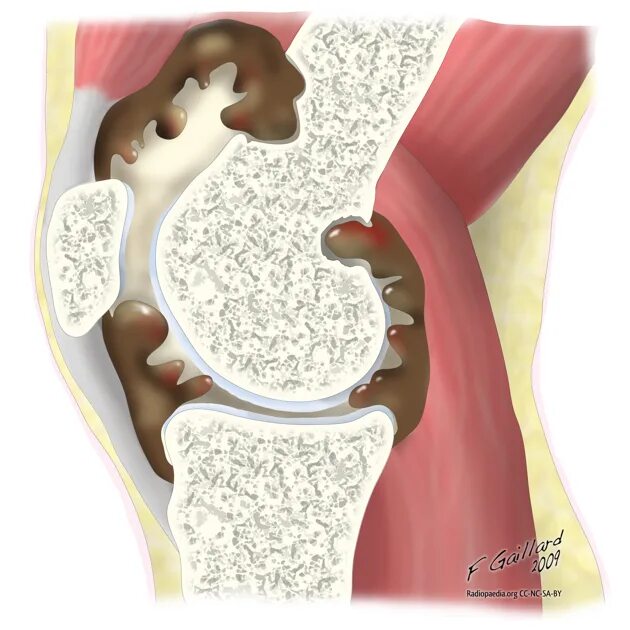

Минимально выраженный синовит